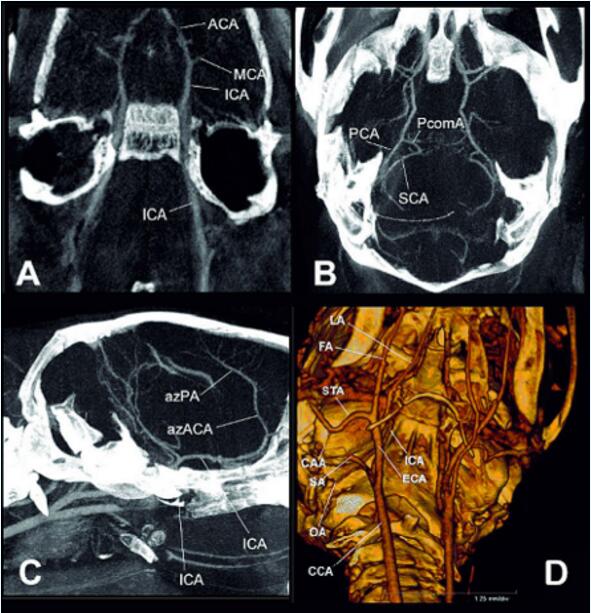

下圖顯示了使用傳統(tǒng)造影劑(Iomerone 300,Bracco Altana)掃描時間為40秒的小鼠顱內和顱外血管的體內數(shù)據(jù)集。這些數(shù)據(jù)集不僅可以分析小鼠不同品系之間腦血管的解剖學差異,還可以評估缺氧和常氧之間的急性血管直徑變化。

圖6  小鼠腦血管數(shù)據(jù)集的最大強度投影(MIP,A-C)和體積渲染(D)。圖像(A)顯示了大腦內部動脈(ICA)通過顱底和Willis圈的情況,其中包括大腦中動脈(MCA)和大動脈。大腦中動脈(MCA)和大腦前動脈(ACA),以彎曲的MIP形式呈現(xiàn)。圖片(B)是BALB/c小鼠的Willis圈的橫向視圖,顯示了大腦后動脈(PCA)、小腦上動脈(SCA)和后交通動脈(PcomA)。圖片(C)表示小鼠腦血管的矢狀圖。小鼠腦血管的矢狀面圖,可見舌周動脈(azPA)的小分支。D)顯示了小鼠顱外血管的體積圖,其中包括頸總動脈(CCA)、顱外動脈(ACA)等動脈。